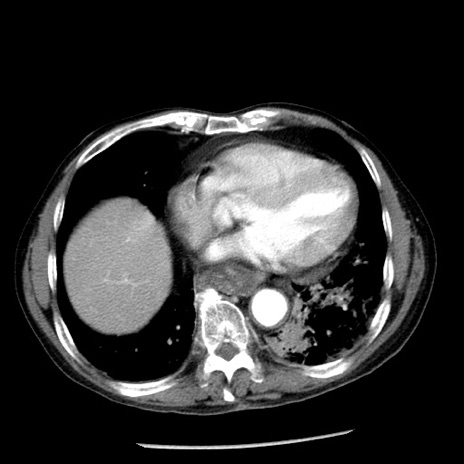

症例26(横断像)

【症例】80歳代男性

【主訴】嘔吐

【現病歴】昨晩2回嘔吐あり、今朝になっても嘔吐あり。来院。

【既往歴】胃潰瘍

【身体所見】意識清明、BT 37.6℃、BP 166/95mmHg、HR 100bpm、SpO2 97%、腹部:平坦・軟、腸蠕動音聴取良好、圧痛なし。

【データ】WBC 21900、CRP 1.46